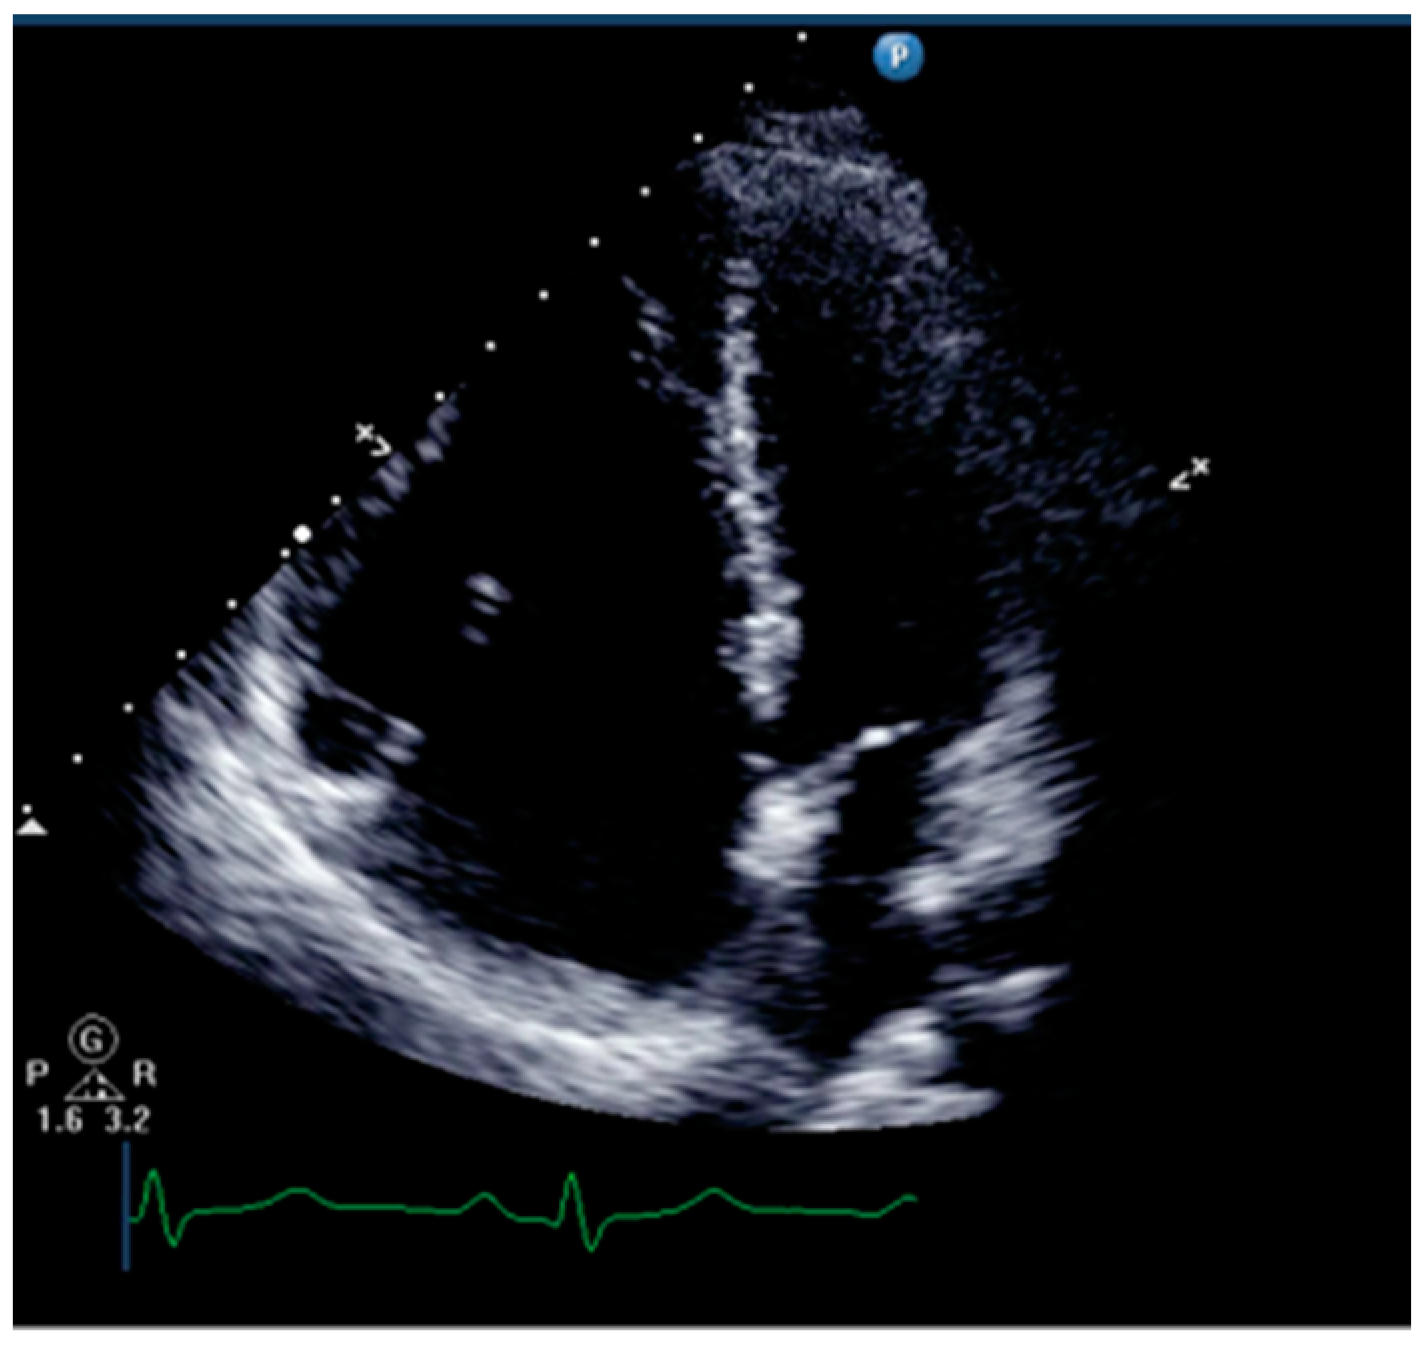

Right ventricular dilatation and paradoxical movement of the interventricular septum are common ultrasound signs of right ventricular dysfunction for qualitative assessment of RV (Figure 3). Physicians can measure the ratio of right ventricular to left ventricular end-diastolic volume in the apical four-chamber view. The RV/LV area ratio over 0.6 indicates right ventricular enlargement, while over 1.0 indicates severe enlargement [14].

Figure 3.

The ultrasound sign of right ventricular dilation.

Paradoxical movement of the ventricular septum is a sign of increased RV preload and afterload, especially afterload. The leftward shift of the interventricular septum can be observed in the short-axis view, causing the left ventricle to be compressed into a “D” shape [14]. It should be noted that not only chronic pulmonary hypertension can cause right ventricular dilation, but when pulmonary artery pressure suddenly increases, the right ventricle can also acutely enlarge.

The size of the right atrium and the thickness of the right ventricular free wall can help distinguish between acute and chronic right heart failure. Right atrium enlargement is often observed in patients with chronic pulmonary hypertension [14]. When the pulmonary artery pressure increases acutely, there is usually no significant right atrium enlargement. The thickness of the right ventricular free wall is usually measured during diastole in the subxiphoid four-chamber view, with a normal thickness of 3–5 mm [19], while in chronic pulmonary arterial hypertension, it can reach 10–11 mm [14].